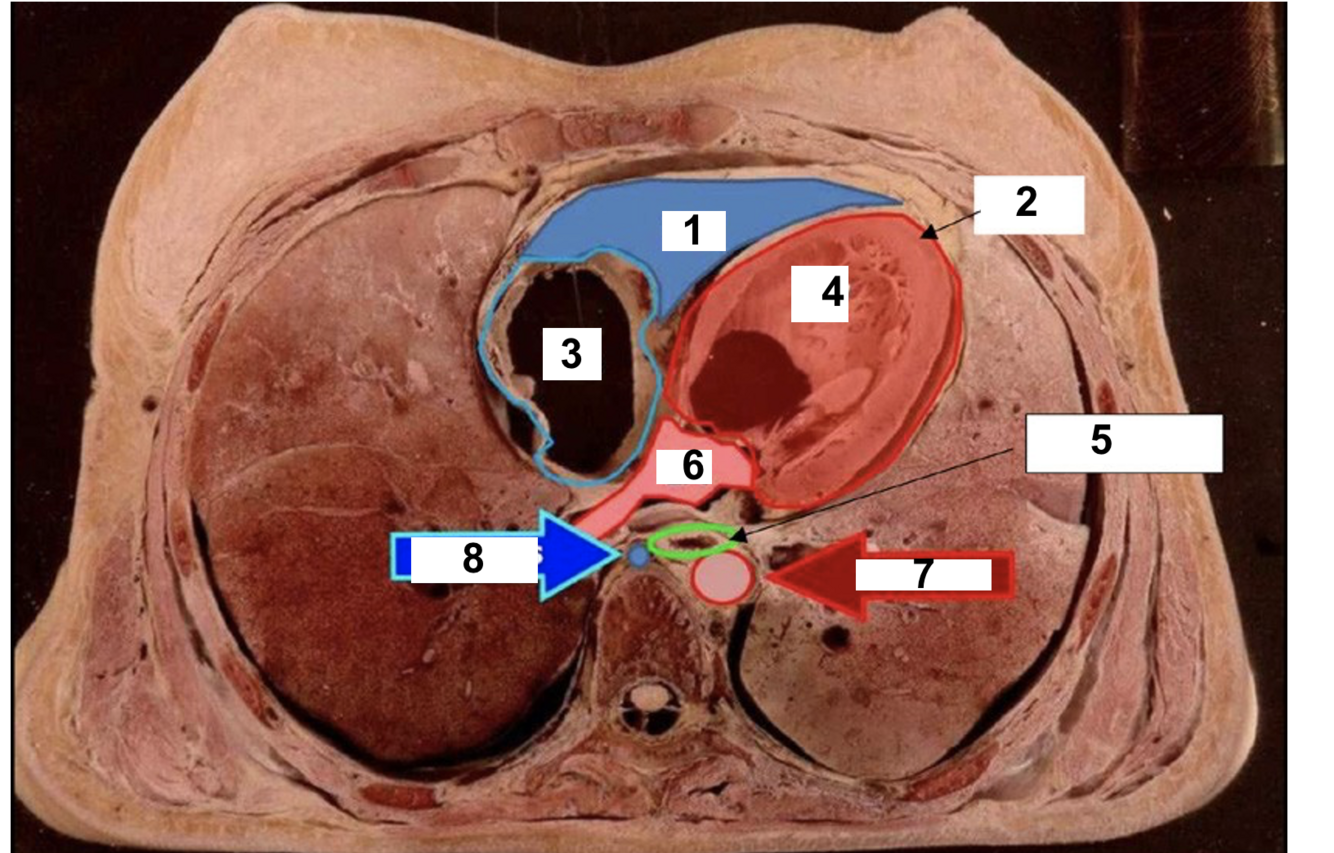

1

Apex

2.

RV

3

RA

4

Ascending aorta

5

LA

6

Descending aorta

7

LV

8

oesphagus